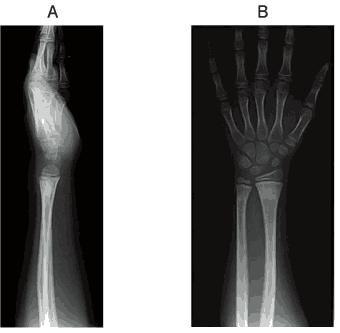

8歳の男児。転んで左手をつき、橈骨遠位部の若木骨折と診断され、副子による3週間の外固定が行われた。固定除去時のエックス線写真(A、B)を示す。手関節には可動域制限が残存している。この時点で行う物理療法で適切でないのはどれか。